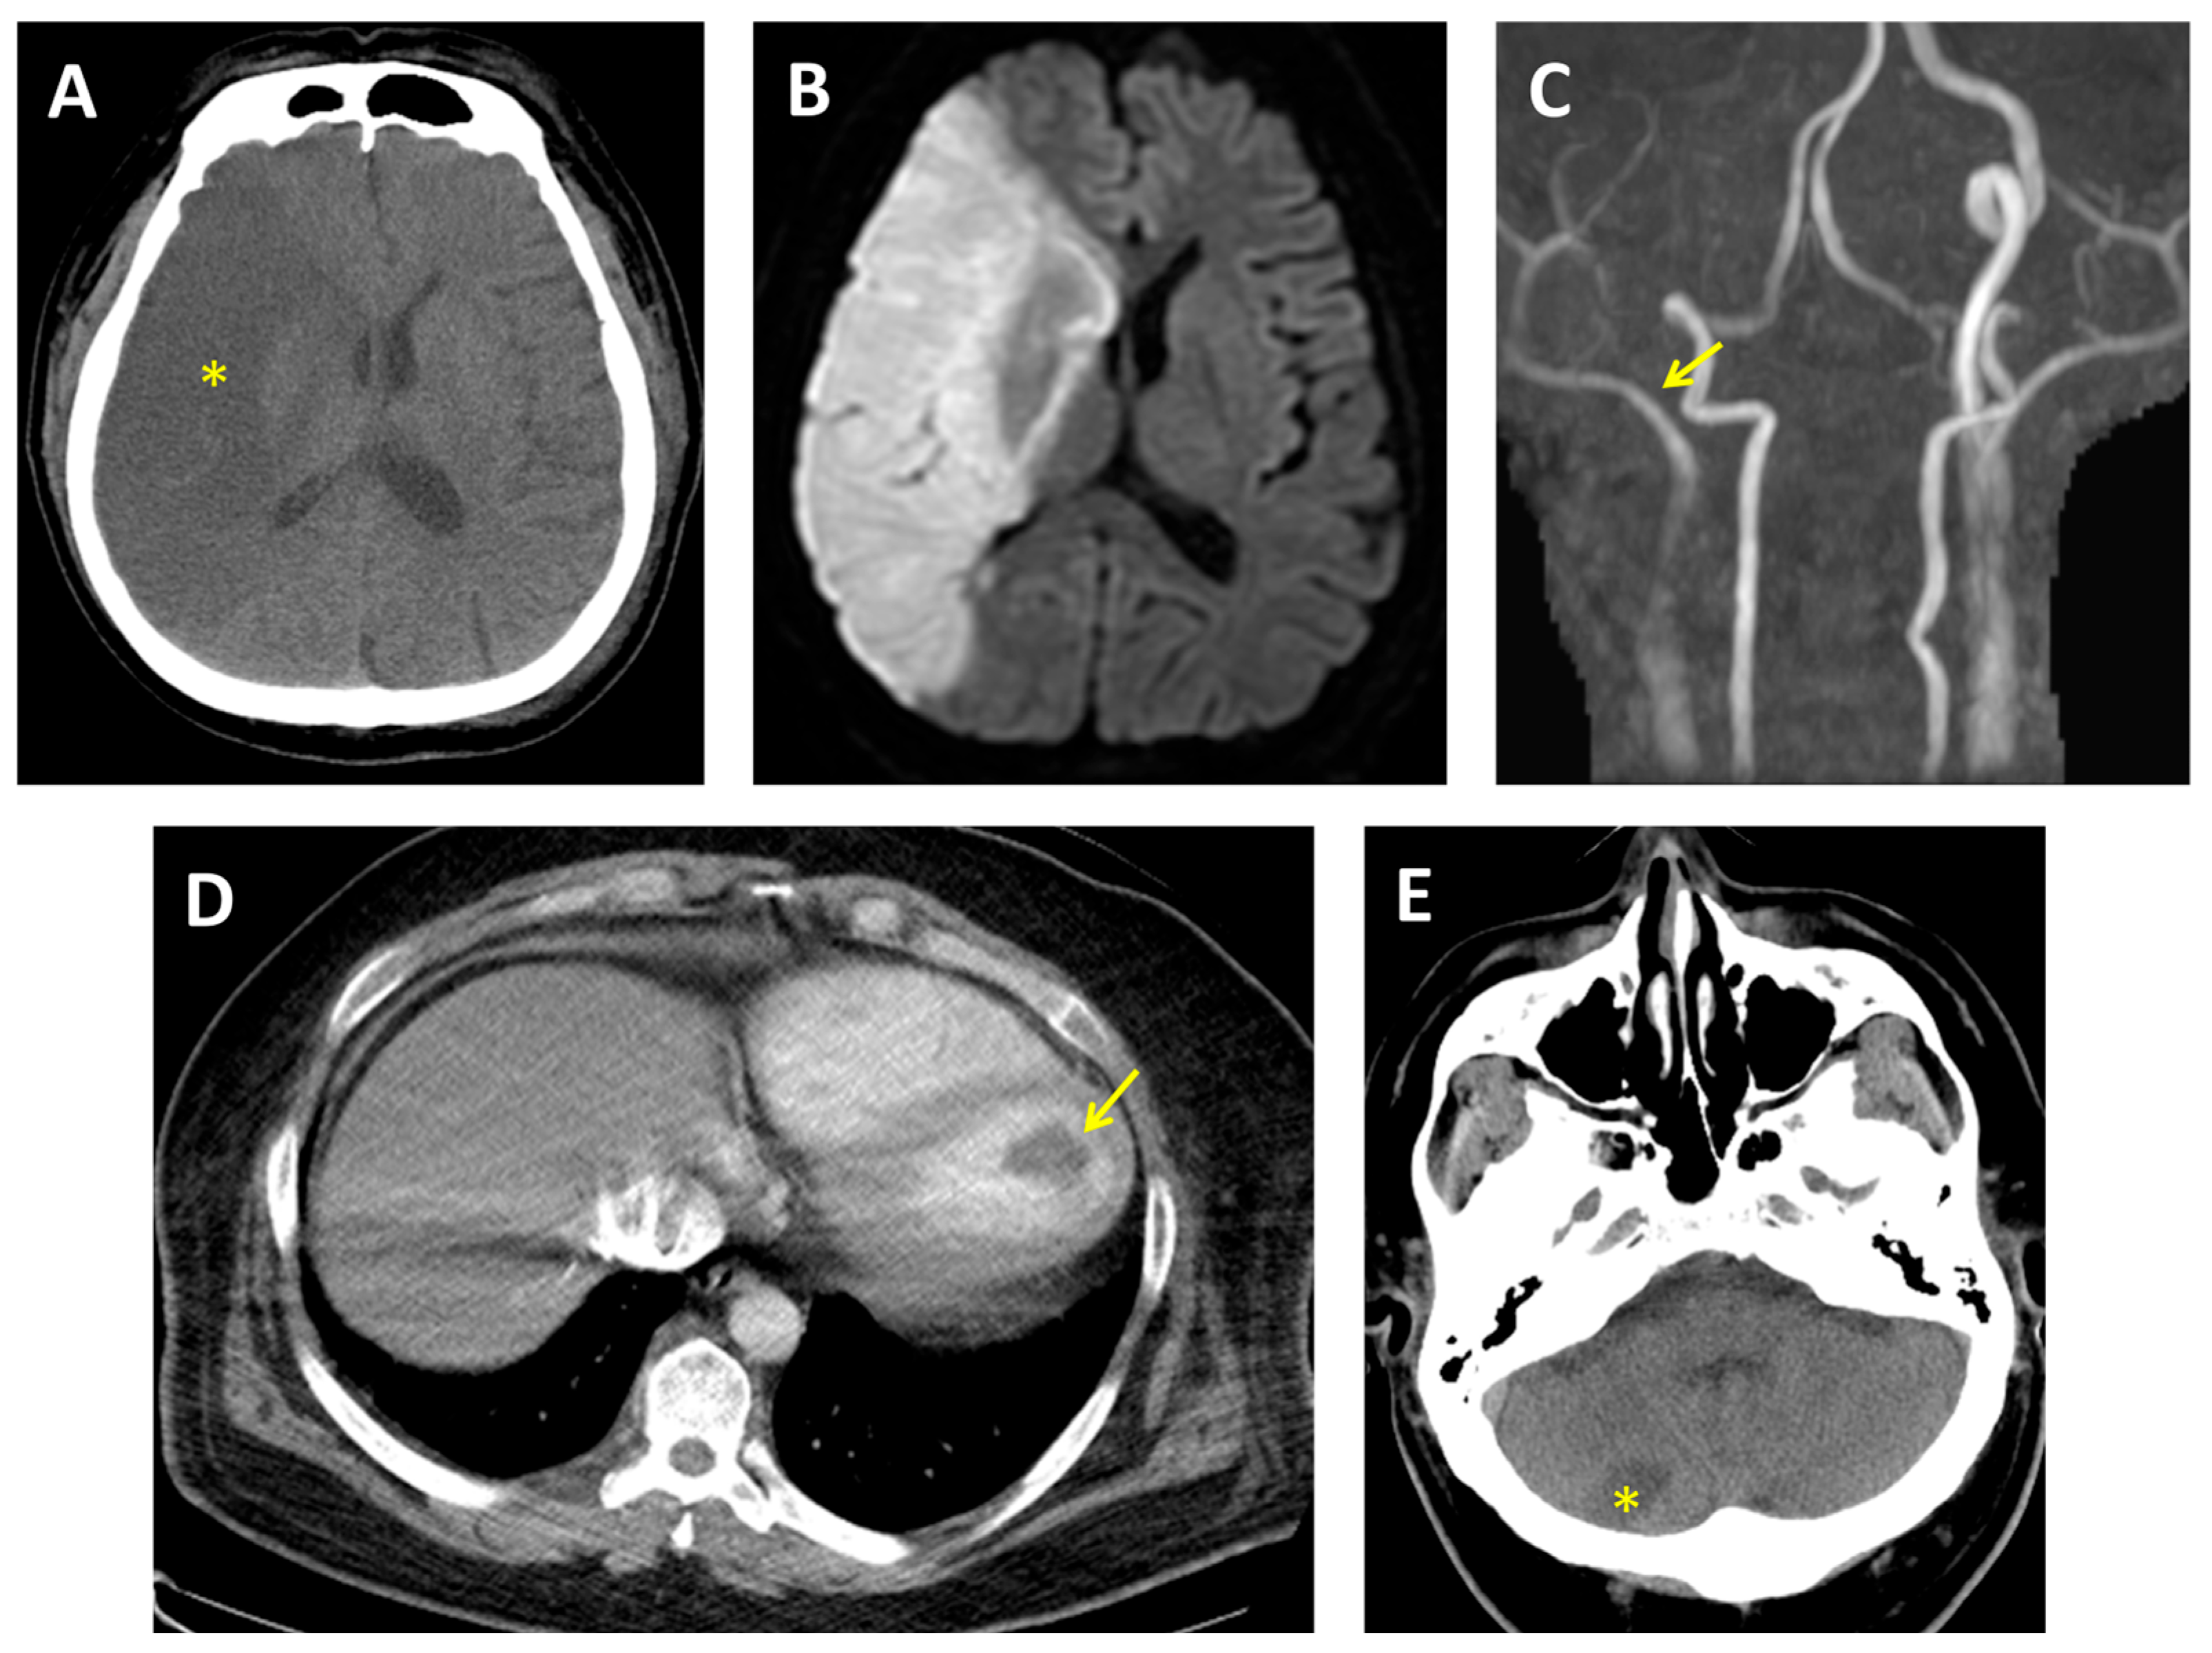

Non-contrast brain CT revealed a large hypodense lesion in the right middle cerebral artery (MCA) territory (Figure 4A). Subsequent diffusion-weighted magnetic resonance imaging (DWI) confirmed acute ischemic infarction (Figure 4B), and magnetic resonance angiography (MRA) demonstrated complete occlusion of the right internal carotid artery (ICA) (Figure 4C). Urine toxicology was positive for MA, and the patient reported daily use for over five years.

Cardiothoracic CT revealed a large thrombus within the left ventricular cavity (Figure 4D). TTE showed four-chamber enlargement and severe systolic dysfunction, with a LVEF of 24%, consistent with MACM. Continuous 24 h ECG monitoring did not detect AF. Laboratory tests revealed an elevated Factor VIII level at 257% (reference range: 60–150%) and a CA-125 level of 168.8 U/mL (normal range: <35.0 U/mL), indicating a hypercoagulable state and increased cardiac filling pressures.

On hospital day 5, the patient developed a new right cerebellar infarction (Figure 4E), indicating ongoing embolic activity. Initial anticoagulation with warfarin was complicated by gastrointestinal bleeding, prompting a switch to rivaroxaban, which was continued without further thromboembolic or bleeding events during hospitalization.

Figure 4. (A) Brain CT initially revealed a right middle cerebral artery territory with a large hypodensity (star). (B) Brain MRI showed hyperintensity on DWI in the same area. (C) MRA showed total occlusion of the right internal carotid artery (arrow). (D) Contrast-enhanced CT of the chest revealed a left ventricular thrombus (arrow). (E) Follow-up brain CT showed a new hypodensity in the right cerebellum (star). CT, computed tomography; DWI, diffusion-weighted imaging; MRA, magnetic resonance angiography; MRI, magnetic resonance imaging.